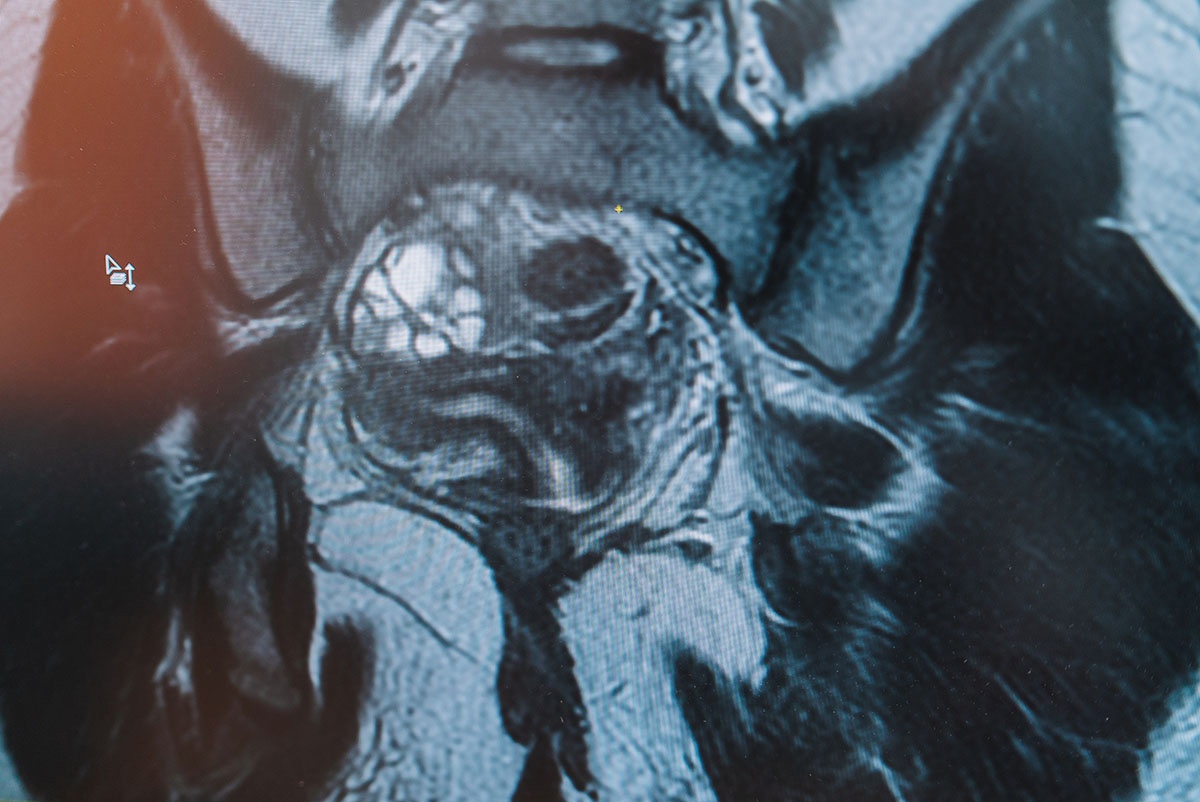

Обследование выявило редкую патологию - рядом с маткой пациентки располагался рудиментарный рог, который не сообщался с полостью основного рога.  Девушку направили на операцию.

- В норме у женщин есть матка, две фаллопиевы трубы и два яичника. В норме у каждой женщины есть матка, две фаллопиевы трубы и два яичника. У пациентки рядом с органом находился несообщающийся рудиментарный рог с наличием эндометрия. В процессе взросления у девочки начались менструации, которые происходили как в матке, так и в рудиментарном роге. На протяжении нескольких месяцев происходило накопление менструальной крови в рудиментарном органе, что и привело к возникновению сильного болевого синдрома внизу живота. В такой ситуации срочно требуется оперативное вмешательство, - рассказала специалист.